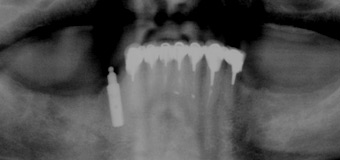

Il me manque de nombreuses dents, les autres sont perdues, je veux l’idéal.

Solution : on peut remplacer toutes vos racines manquantes ou perdues par autant de racines artificielles et vous redonner des dents fixes partout.

Toutes dents sont hélas perdues. Toutes les dents absentes sont remplacées par des couronnes sur implants.